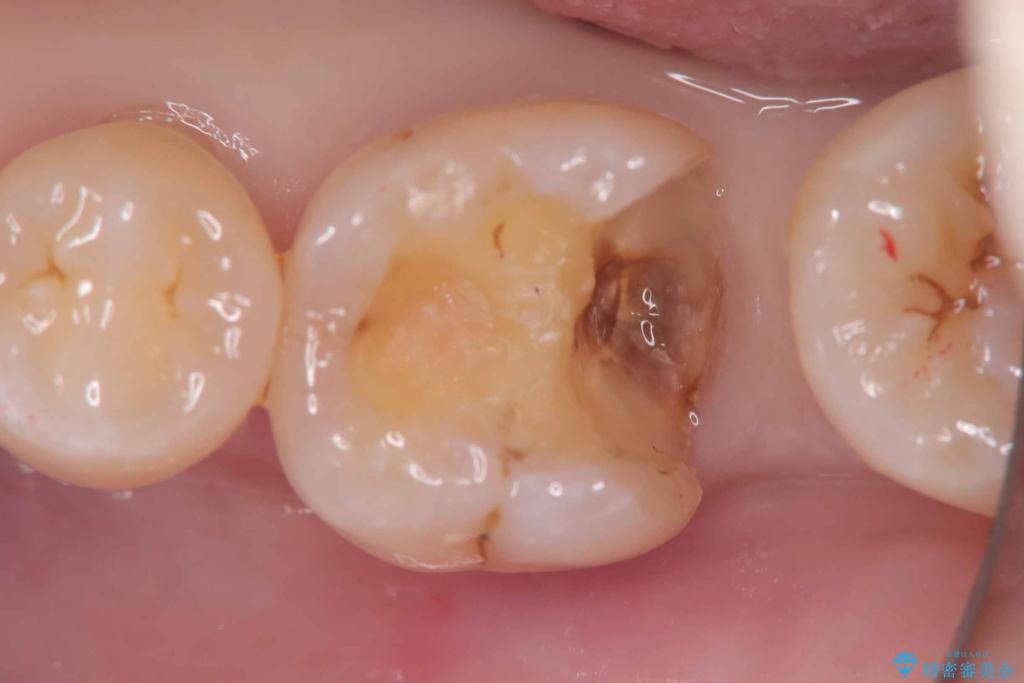

銀歯の下の虫歯|生活歯髄療法|VPT|神経を残すための治療|セラッミクインレー

- 銀歯の下に虫歯が見つかりました。一度治療されている歯であり、レントゲン上では虫歯が神経に近い位置まで進行している様子が確認されました。

ただし、自発痛の既往はなく、歯髄診の結果も正常であったため、虫歯除去中に露髄した場合には生活歯髄療法(VPT)を行う方針としました。

実際の治療ではVPTを施行し、その後痛みなどの症状もなく経過は良好でしたので、最終的にセラミックインレーによる修復を行いました。